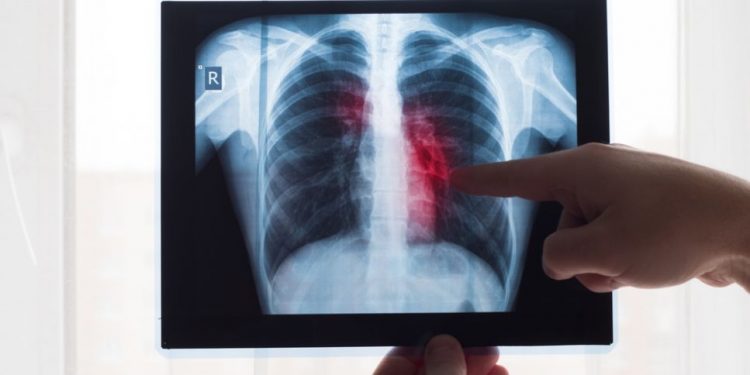

Stage 4 lung cancer survival rates vary depending on the location and type of cancer. The most common types of lung cancer are non-small cell lung cancer (NSLC) and small cell lung cancer. NSCLC is further divided into subtypes, which each have their own unique survival rates.

When NSCLC reaches stage 4, it often spreads to other areas of the body, called distant metastasis. The five-year relative survival rate for NSCLC in stage 4 that has spread to distant organs or regions is just 3 percent, according to the American Cancer Society.